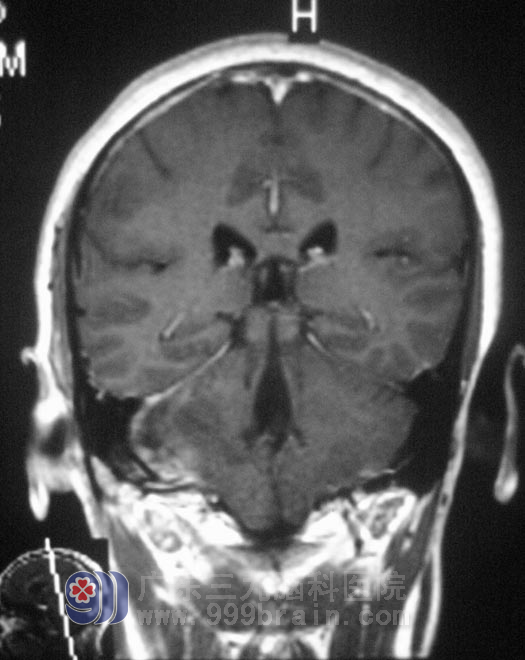

在广东三九脑科医院综合神经外科就诊,头颅MR提示:右侧桥小脑角区占位,大小53.2mm×26.1mm×49.9mm,初步考虑为听神经瘤。在五官科治疗5年无果,祸根竟然又是脑肿瘤。

10月11日,鲁明主任主刀,在显微镜下行右侧桥小脑角占位性病变切除术,术中见肿瘤边界清楚,呈囊实性,部分质韧,血供丰富,分块大部分切除肿块,小部分肿物与脑干及后组颅神经粘连紧密,经过慎重考虑行部分切除术,对后组颅神经保护完好,修补硬膜,顺利结束手术。两天后复查MR示肿瘤基本切除。术后病理结果为:(右侧桥小脑区)神经鞘瘤(听神经瘤)。